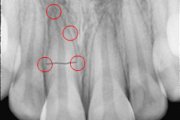

Trauma klassifikatsioon 2 (Mitsuhiro Tsukiboshi,DDS)